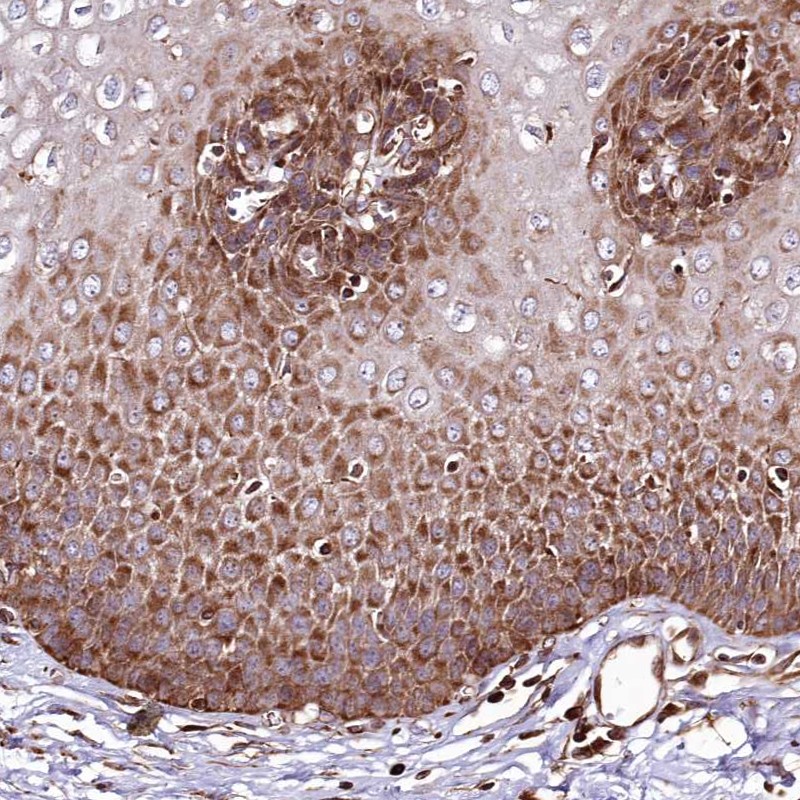

Immunohistochemical staining of human esophagus shows strong cytoplasmic positivity in squamous epithelial cells.